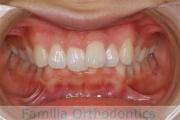

歯並びを綺麗にしたいということで来院されました。叢生(でこぼこ、凹凸、ガタガタ)と上下顎前突のため、上下左右から小臼歯を抜歯の上で、歯科矯正用アンカースクリューを併用したマルチブラケット法を行いました。約2年半、30回の通院が必要でした。

上下とも叢生がありますので、後戻りのリスクがあります。